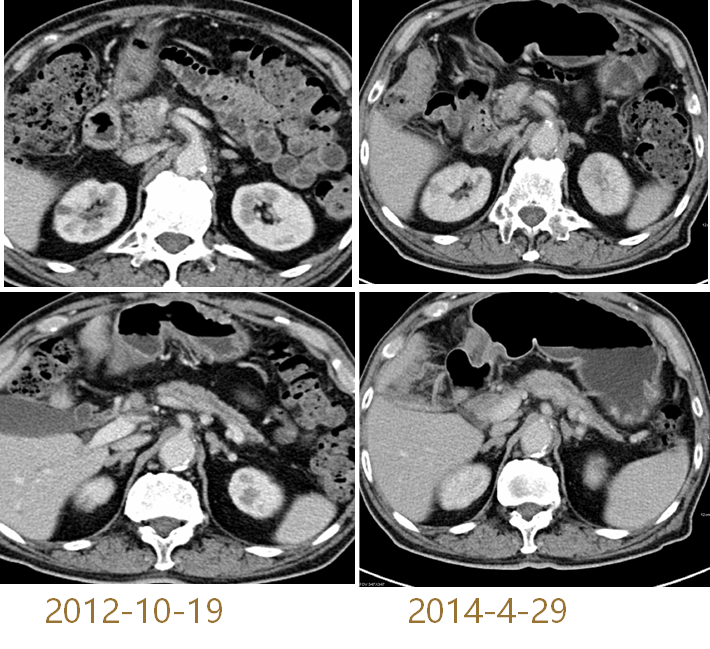

与前片比较,未行任何治疗,胰头体积缩小,胰管扩张减轻,最后临床诊断慢性局灶性胰腺炎。最终影像学战胜病理诊断!

图20 患者胰腺影像检查图

(2012-10-19 VS. 2014-4-29 )